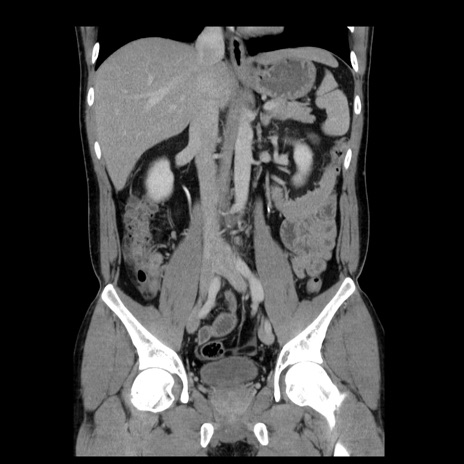

症例4(冠状断像)

【症例】30歳代男性

【主訴】腹痛、嘔吐

【現病歴】昨晩から突然の腹痛あり、その後嘔吐、軟便も出現。腹痛が改善しないため救急搬送となる。2日前にしめ鯖の食事歴あり。

【身体所見】意識清明、苦悶様、BP 135/90mmHg、BT 35.7℃、腹部:平坦、やや硬、心窩部〜臍部に自発痛、圧痛あり、筋性防御+、反跳痛-

【データ】WBC 8100、CRP 0.57